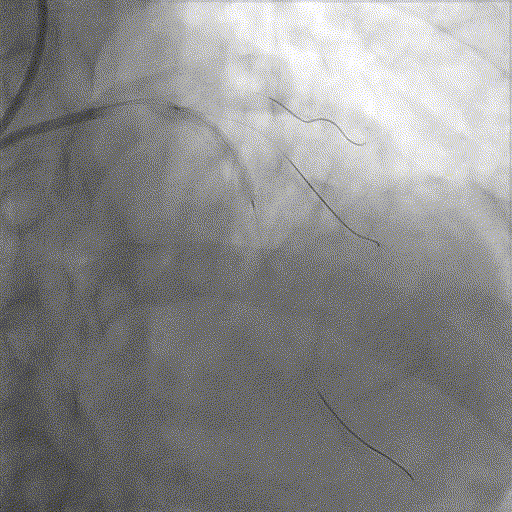

基础造影

右冠状动脉近段基本正常,中段狭窄50%,远段原支架通畅,右冠-后降支开口狭窄70%;左主干狭窄40%;前降支近中段全程弥漫性钙化病变,狭窄80-99%,第一对角支狭窄60%,第二对角支狭窄80%;回旋支近段基本正常,远段狭窄60%。